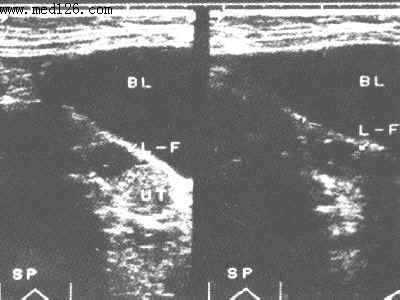

6成熟卵泡超声显像图

膀胱(BL) 子宫(UT) 左侧卵泡(L-F)